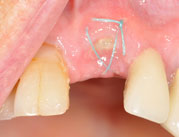

Case Report

Tentpole-Technik unterstützt durch vernetzte Hyaluronsäure Dr. Alexander Müller-Busch |